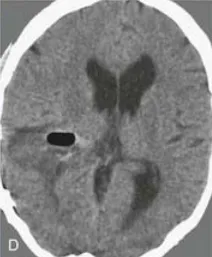

A与B:术前轴位增强T1加权MRI

术后CT证实无残留(D)